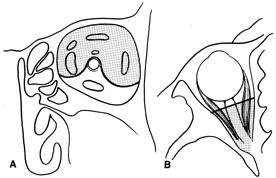

complete hemostasis. Indications Lateral orbitotomy provides excellent access to deep lesions in the subperiosteal, peripheral, or

intraconal space lateral to the optic nerve (Fig. 8A, B).  Fig. 8. Coronal (A) and axial (B) views in an illustration of areas (shaded) amenable to lateral

orbitotomy. Fig. 8. Coronal (A) and axial (B) views in an illustration of areas (shaded) amenable to lateral

orbitotomy.

function usually recovers unless the nerves have been transected. Indications Transcranial orbitotomy provides access to the superior two-thirds of all

the orbital compartments (Fig. 15). In some cases, the craniotomy is used only to provide access to

the orbit that is otherwise not possible, such as biopsy of an orbital

apex mass. Its primary use is for exploration of tumors involving the

orbital apex, or large tumors extending above and medial to the optic

nerve. The transcranial orbitotomy also is used as part of combined

procedures for approaching tumors involving the orbit as well as the anterior

and middle cranial fossae. Most commonly, this involves sphenoid

wing meningioma resection.  Fig. 15. Schematic of areas amenable to transcranial orbitotomy. Coronal (A) and axial (B) sections. Fig. 15. Schematic of areas amenable to transcranial orbitotomy. Coronal (A) and axial (B) sections.